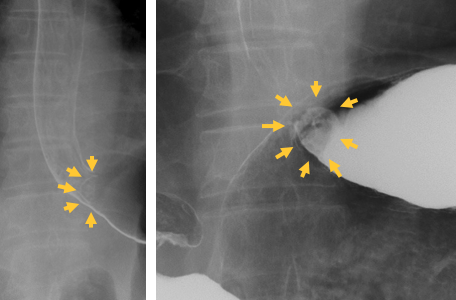

健康診断の胃カメラで胃の入り口(噴門といいます)に表面がゴツゴツとした盛り上がりが見つかりました。細胞を取ってみると、胃がんの細胞が見つかりました。

患者様は当初胃カメラによる切除を希望されましたが、超音波検査でがんの根が粘膜の下まで入り込んでいるため、胃カメラによる切除では治療が不十分になる可能性がありました。

通常この位置のがんは胃を全部取ることが多いのですが、病変が早期で小さく、胃を残して欲しいという患者様の希望もあり、胃の上半分を切除する(噴門側胃切除術といいます)ことにしました。

バリウム検査でも食道と胃のちょうど境目に病気があるのがわかります。